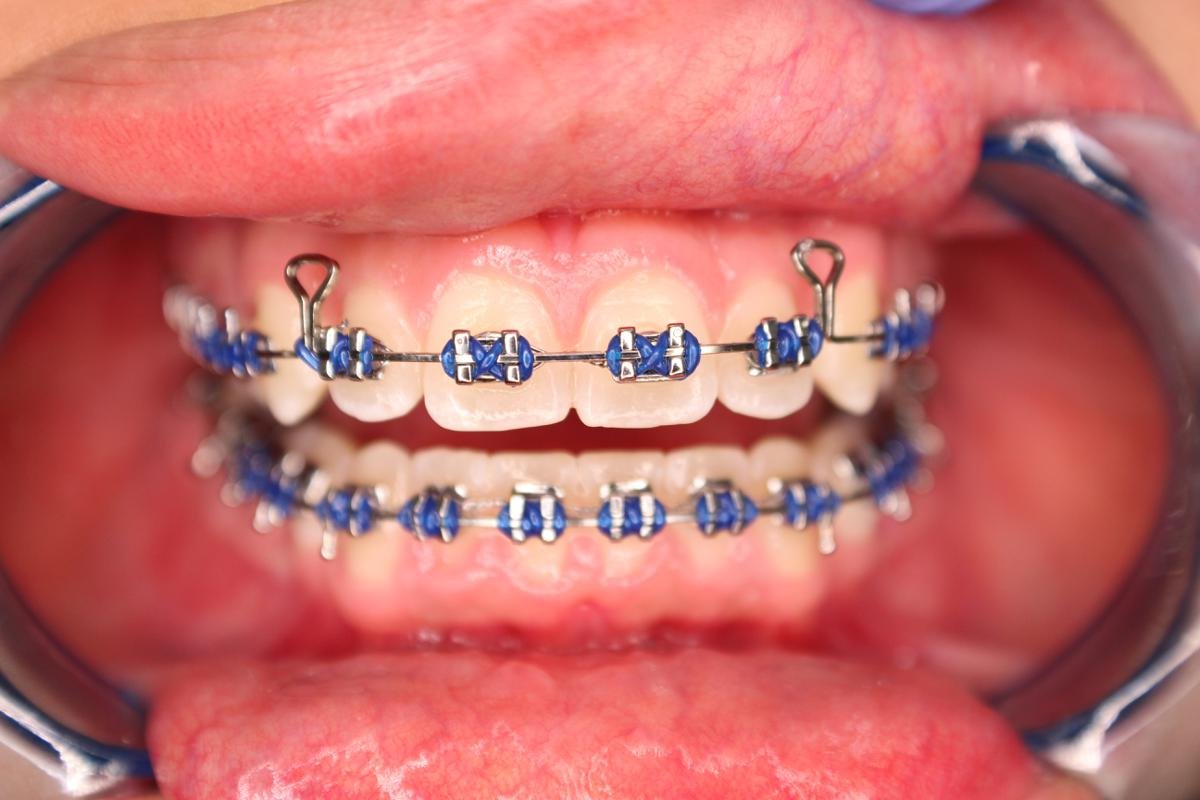

Many of us are not born with picture perfect teeth. For the straight teeth and alignment many people are searching for, braces is a common and effective treatment. Precision Dental Care uses the latest X-Ray technology to trace and model your teeth for your unique dental needs. From crooked teeth to alignment issues, braces can solve a variety of oral concerns.

Dr. Fonseca has years of experience so you can count count on the results you want. Trust our team to guide you through the experience every step of the way for a comfortable fit.